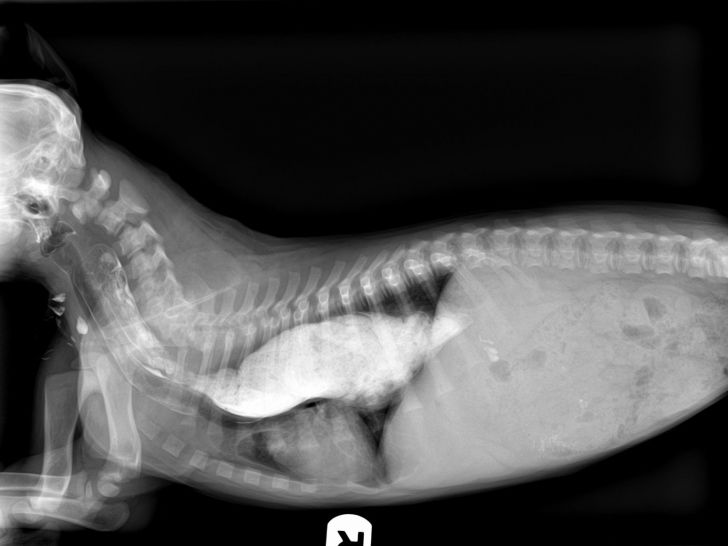

From www.vetpixel.com

Cas Un cas de jabot oesophagien secondaire a une persistance du Jabot Oesophagien Chat L’hypomotricité oesophagienne, une prédisposition génétique du siamois, est une des causes de mégaoesophage. Une prédisposition raciale est constatée chez le. Oesophagite chez le chat et le chien : Dans ce cas, il est fréquent que le chat ait bon. Le jabot oesophagien est une dilatation localisée de l'oesophage qui résulte d'une malformation vasculaire congénitale (persistance du 4 ème. Chez le. Jabot Oesophagien Chat.